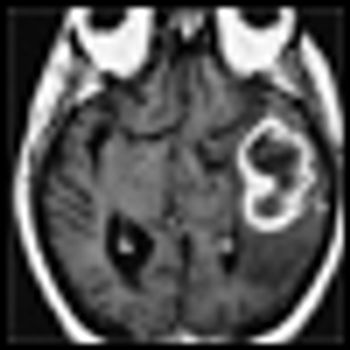

The patient is a 58-year-old woman who was diagnosed at an outside hospital with a World Health Organization (WHO) grade III non–contrast-enhancing right frontal anaplastic astrocytoma, with spread into the genu of the corpus callosum.